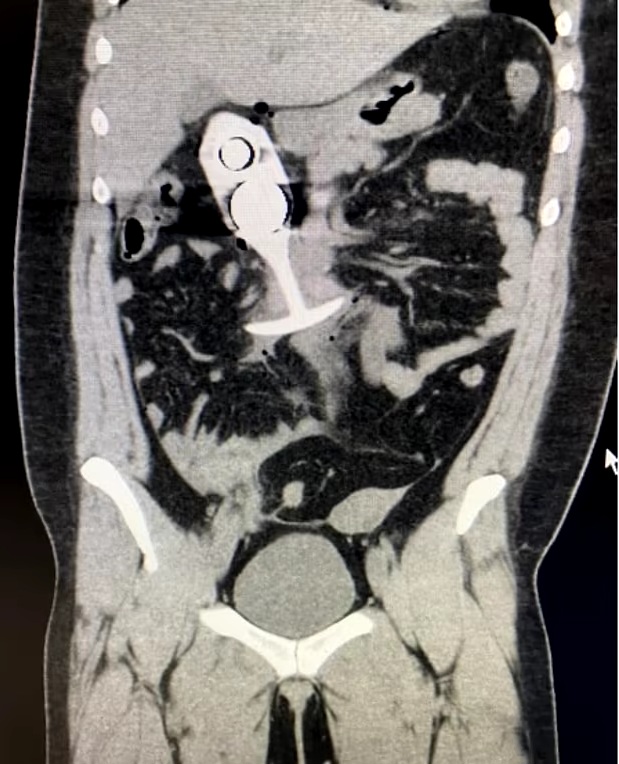

A woman reportedly suffered major injuries after she mistakenly left a sex toy in their rectum while undergoing an MRI scan.

According to the report, the sex toy that was left in the rectum of the patient resulted in a hazardous reaction between the powerful magnets and the metal parts of the toy.

According to the scan image result shared online, the sex toy injured the patient causing potentially damaging organs and tissue along the way.

Reports say that the powerful magnetic forces used to create an MRI’s detailed scans reportedly pulled the metallic core of the silicone toy through the patient’s rectum and up into their chest cavity at the “speed of sound”.

See the scan image below…